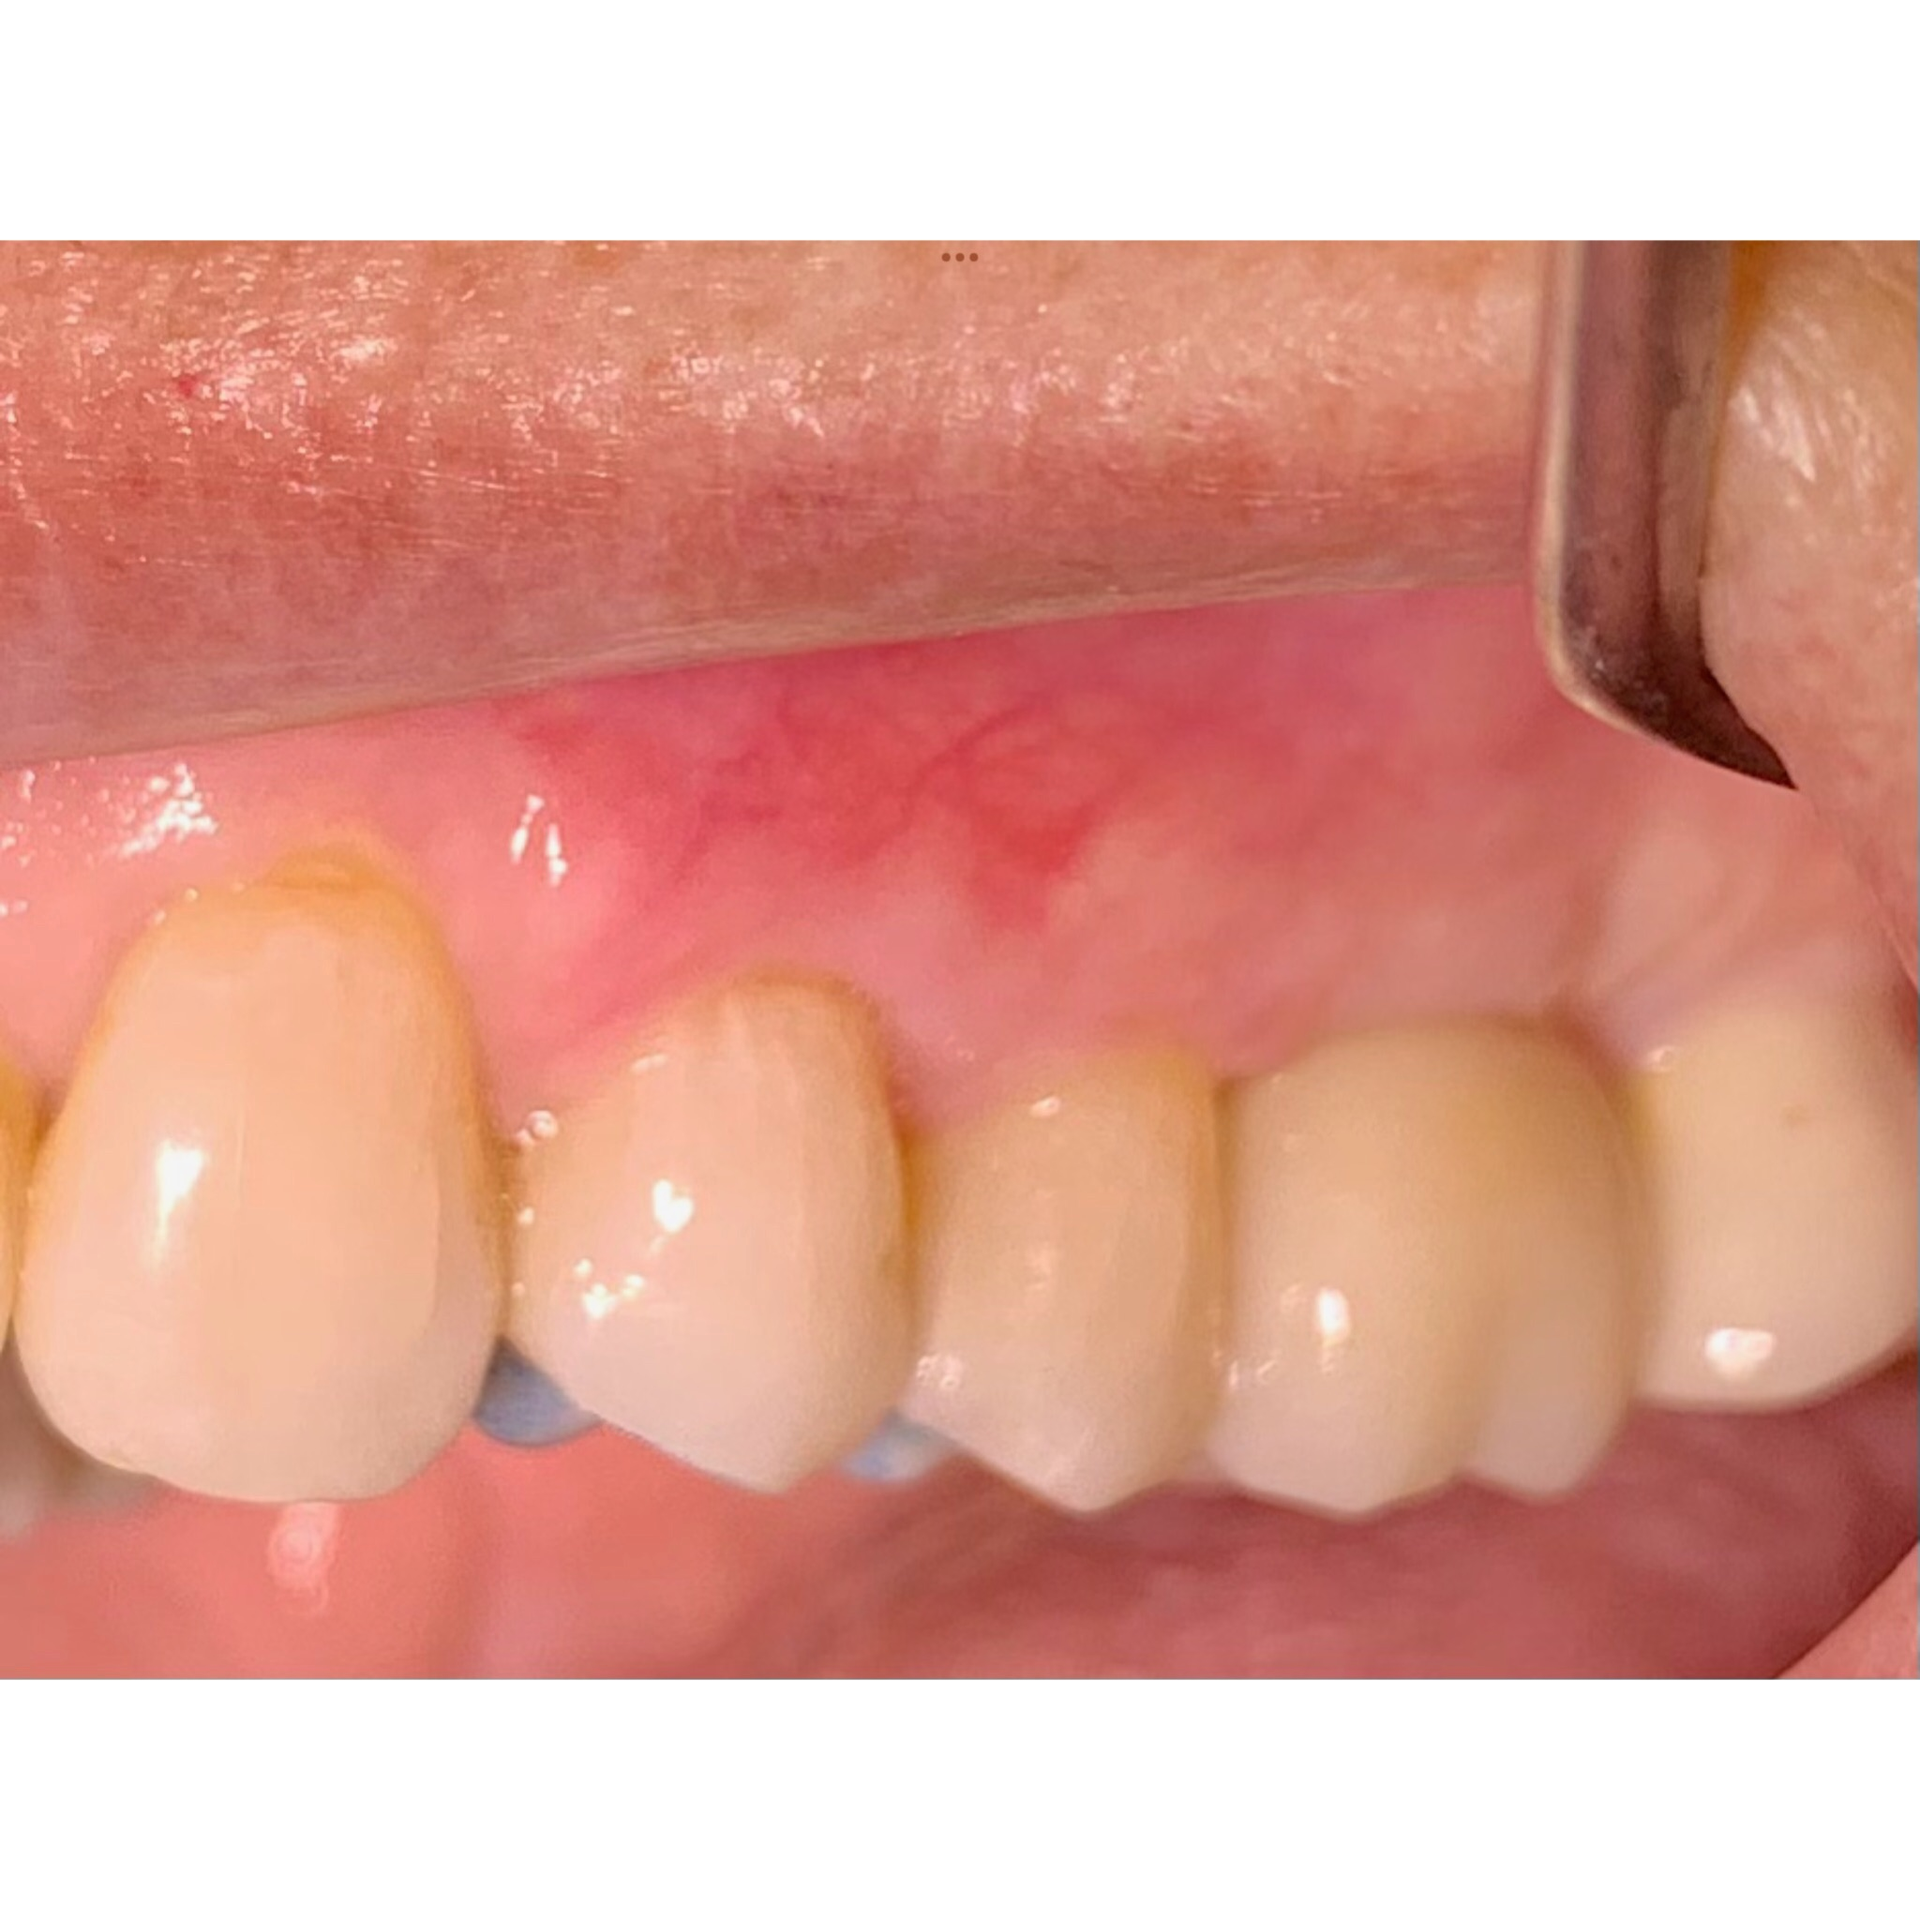

Avant et après greffe de gencive